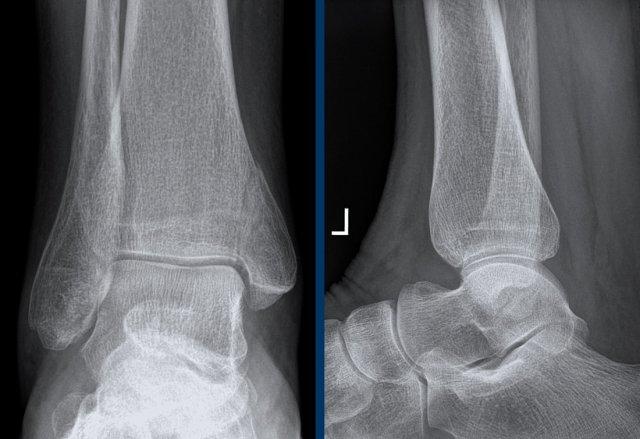

Ca 1 – Chấn thương cổ chân

Hình ảnh cho thấy những dấu hiệu gì và có ý nghĩa như thế nào?

Nhấp vào hình ảnh để xem phóng to.